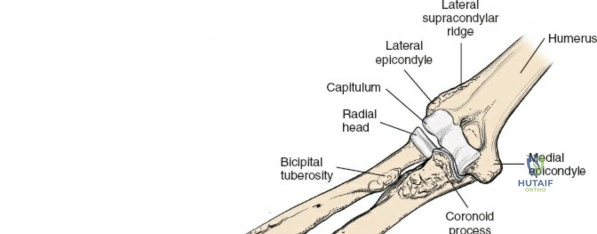

Osteology and Biomechanics of the Proximal Radius

The radius and ulna function together as a highly coordinated articular quadrangle. The proximal radius consists of the radial head, which articulates with the capitellum; the radial neck; and the bicipital tuberosity, which serves as the insertion site for the biceps brachii tendon. The biomechanics of the forearm dictate that the radius rotates around the stationary ulna during pronation and supination. The normal lateral curvature of the radius—the radial bow—is critical for this rotational clearance. Any surgical approach to the proximal radius must allow for the precise restoration of this bow, as even a minor malreduction can lead to profound deficits in forearm rotation.

The posterior interosseous nerve is the single most important structure left vulnerable during exposure of the proximal radius. A branch of the radial nerve, the PIN dives into the supinator muscle through the Arcade of Frohse. It travels obliquely and spirally around the radial neck and proximal shaft within the substance of the supinator. In approximately 25% of patients, the nerve comes into direct contact with the posterior periosteum of the radial neck. Therefore, any blind placement of retractors around the posterior aspect of the proximal radius is strictly contraindicated, as it can easily crush the nerve against the bone, resulting in devastating loss of finger and thumb extension.